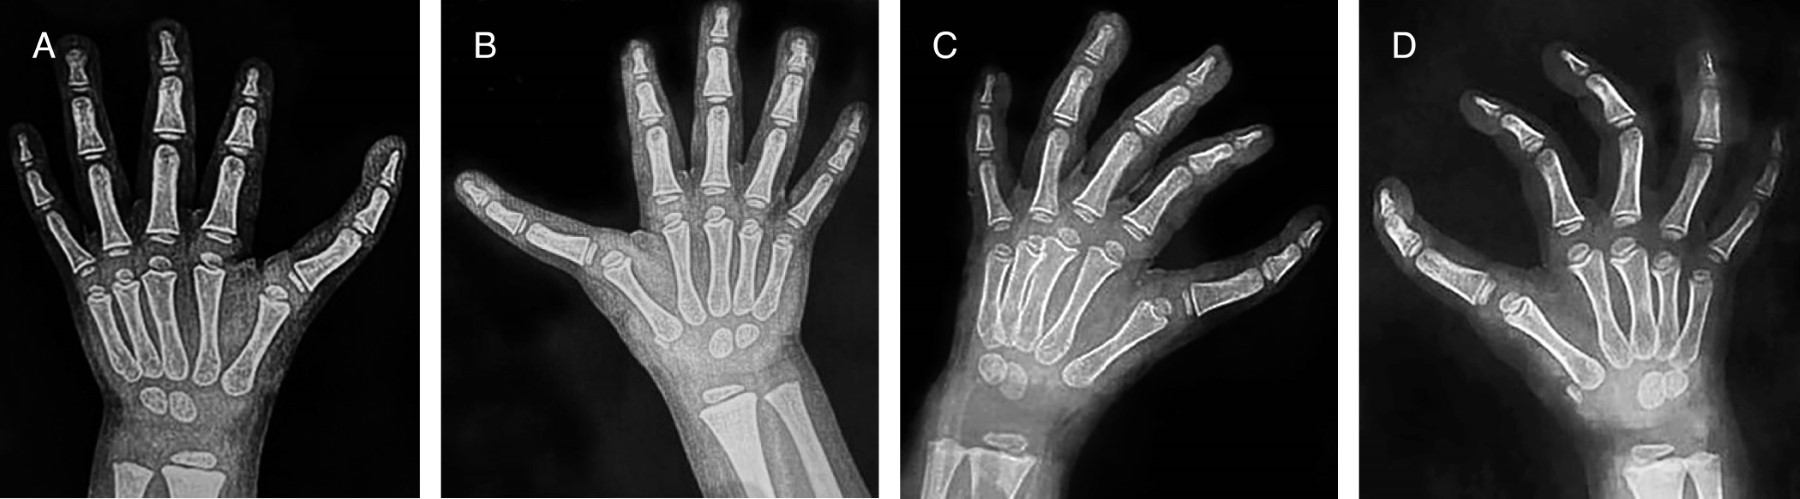

Un año después de la primera cirugía se observa presencia de pulgar trifalángico bilateral, con actitud en rotación externa de ambos pulgares con dificultar para la oposición y movimientos de pinza gruesa y fina, se solicitan radiografías dorso-palmares y oblicuas de mano observando consolidación total de ambos metacarpianos. Dos años posteriores acude a consulta de seguimiento donde se observa radiográficamente una consolidación total de primer metacarpiano bilateral, así como la presencia de una falange intermedia tipo rectangular (Figura 3), clínicamente se observa en ambas manos presencia de pulgar trifalángico, con dedo en actitud de rotación externa con dificultad para la oposición, con una longitud similar a dedo índice (Figura 4).